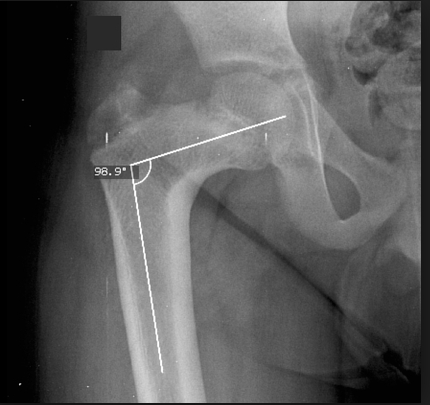

Complications of osteopetrosis include osteomyelitis, long bone fractures, and coxa vara (a decrease in the normal angle between the femoral head and shaft).